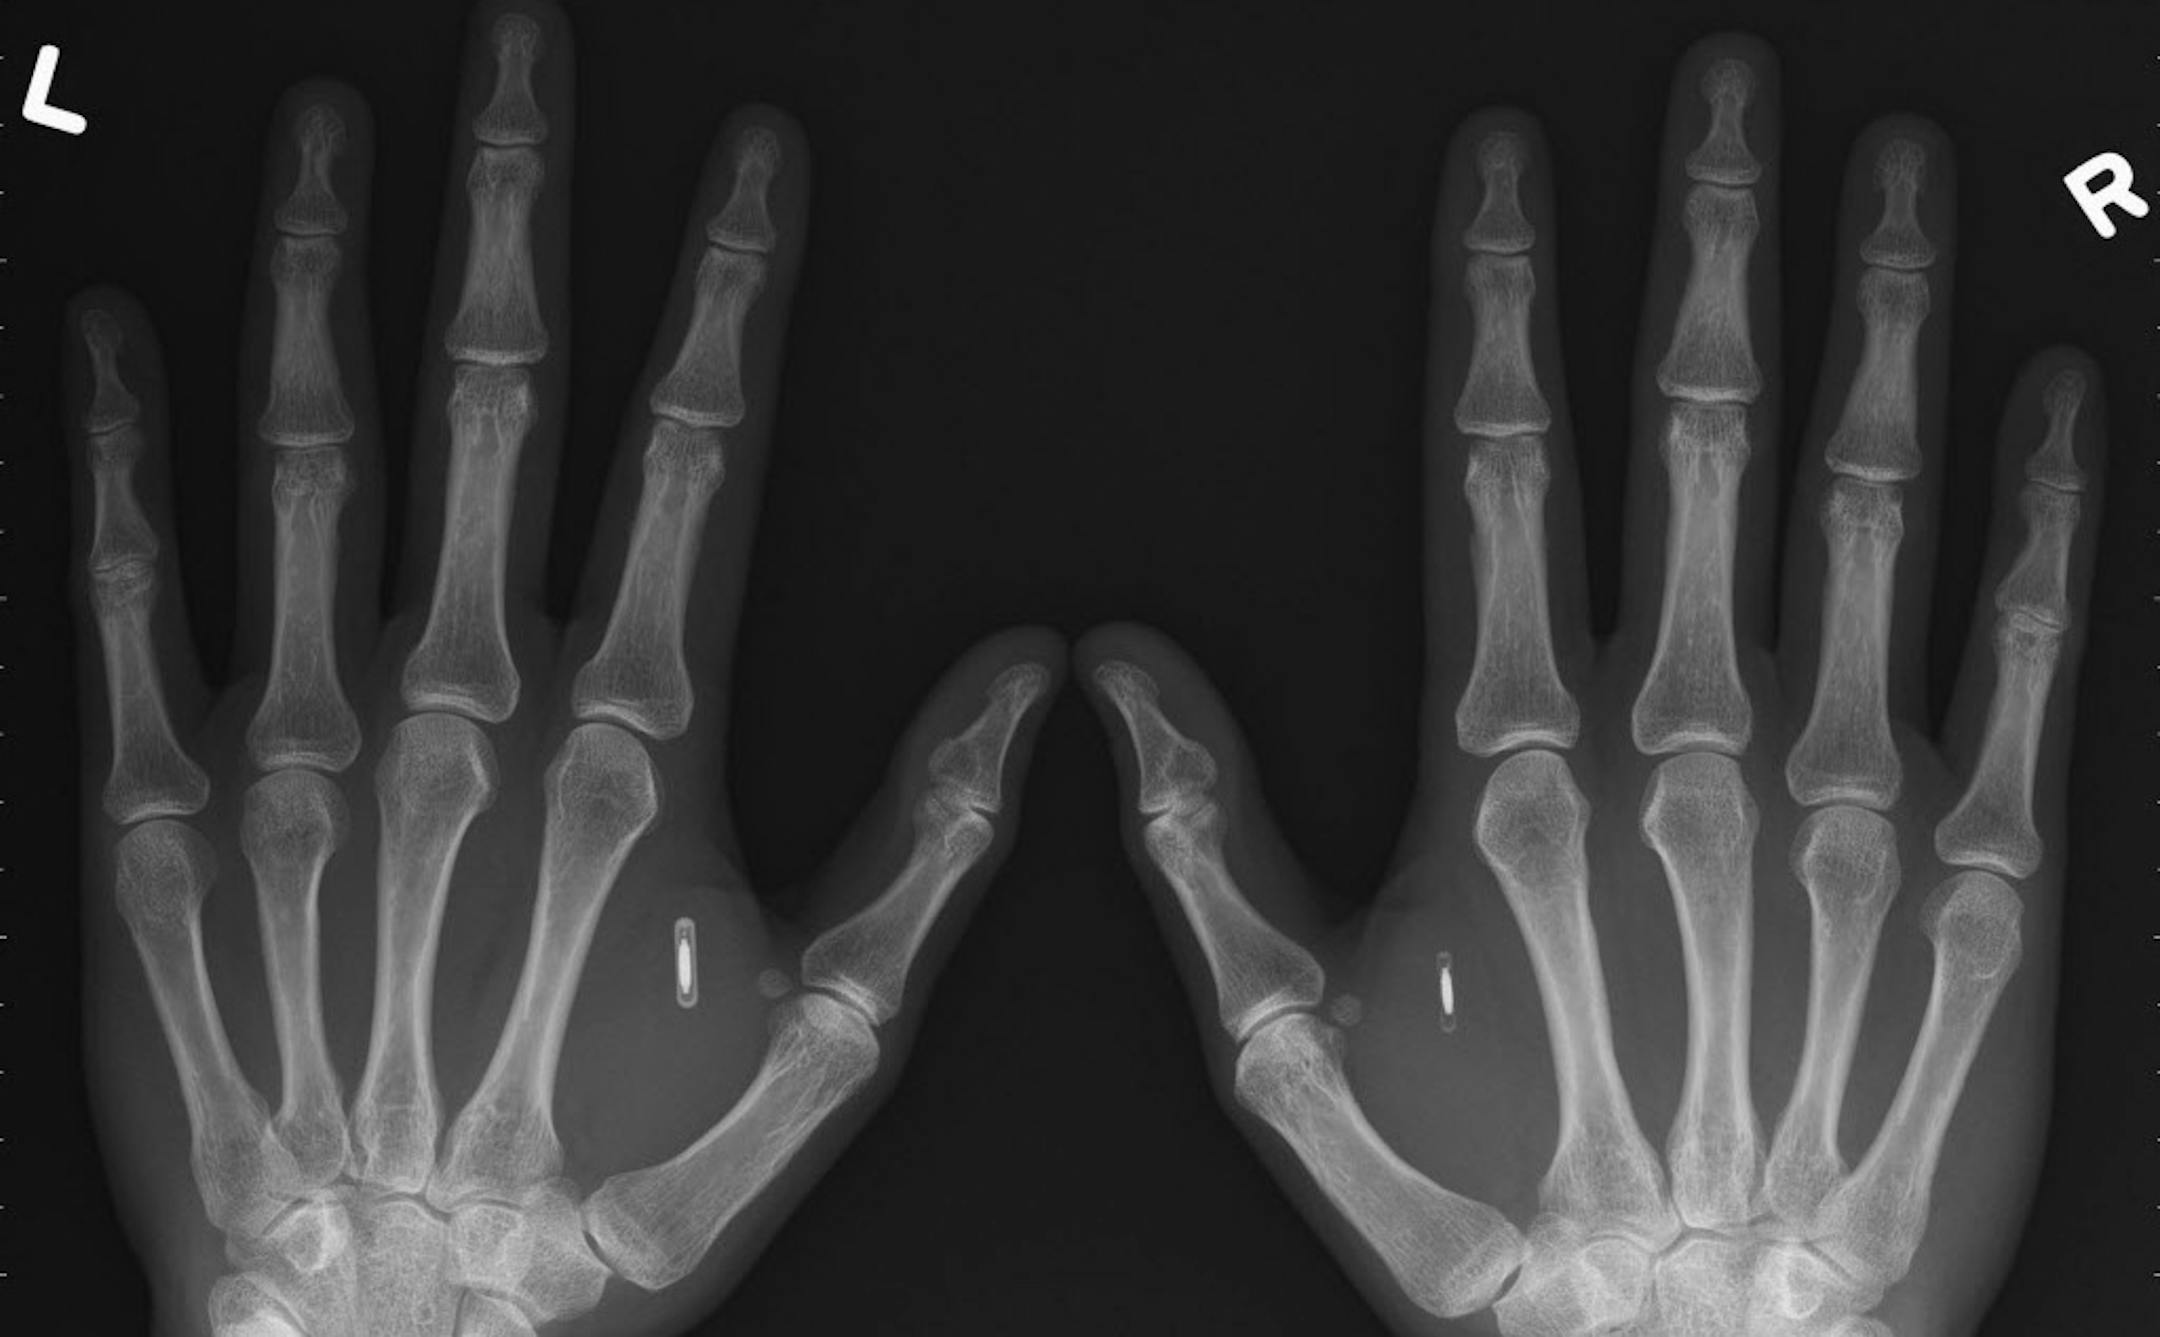

This X-ray depicts the hands of Amal Graafstra, founder of Dangerous Things. He has had two radio frequency identifier inplants in his hands which he uses to unlock his car, computer and door to his Seattle home. (Courtesy of Amal Graafstra/MCT) ORG XMIT: 1147011

Provided by Amal Graafstra An X-ray shows the radio-frequency identifier implants Amal Graafstra, founder of Dangerous Things, uses to unlock his car, computer and home in Seattle. (The Minnesota Star Tribune)

The 37-year-old doesn't need a key or password to get into his car, home or computer. He's programmed them to unlock at the mere wave of his hands, which are implanted with radio frequency identification tags. The rice-size gadgets work so well, the Seattle resident says, he's sold similar ones to more than 500 customers through his company, Dangerous Things.